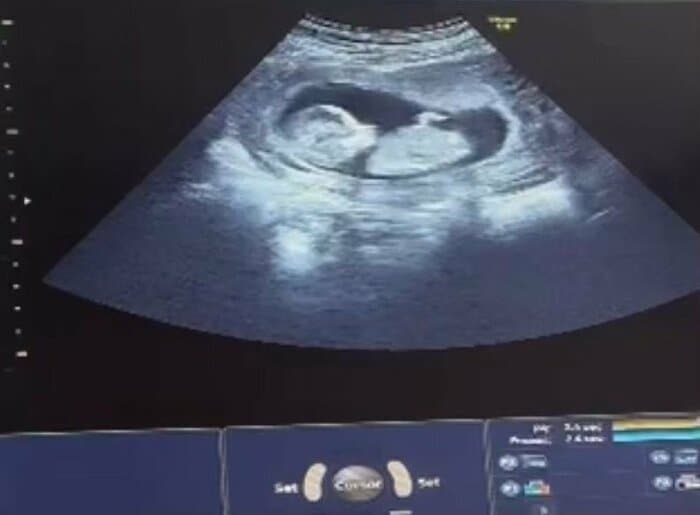

送信元は、欧州とアジアの境界に位置する国、ジョージア。添付された動画を開くと、黒い背景の中で、淡い白色のソラマメのような輪郭が脈打った。

数千キロ離れた異国の地で、見知らぬ女性の子宮で育つ「我が子」のエコー動画。夫婦の指先が、ガラス画面に映る命の鼓動をそっとなぞった。